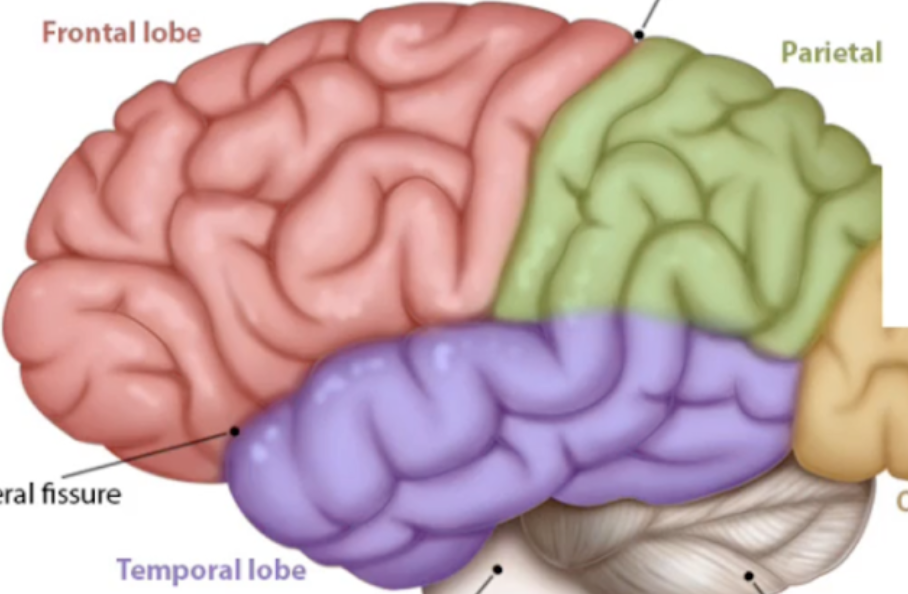

What are the ridges (folds) on the cerebrum called?

Gyrus/Gyri (Peak of the sunchip)

What are the grooves(valley) on the cerebrum called?

Sulcus/Sulci valley between the peak

Lobe function: motor speech,memory formation,personality,Emotion

Frontal Lobe

Lobe function: Somatosensory cortex(sense processing), Sensory integration, Spatial awareness

Parietal Lobe

Lobe function: Visual processing and storing visual memories (posterior side)

Occipital Lobe

Lobe functuon haering, language, smell

Temporal lobe